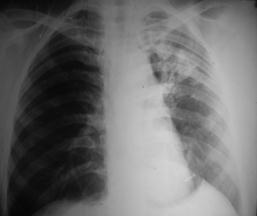

Рис. 7. Обширное затемнение (

экссудативный плеврит

): смещение органов средостения в противоположную сторону